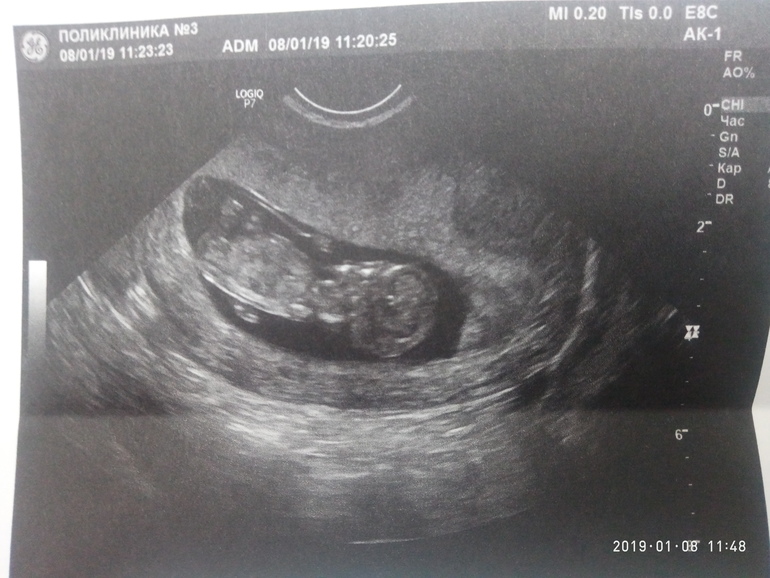

Узи 11 нед и 1 день.

УЗИ, КТГ, доплерМои переживания о ЗБ не подтвердили, слава Богу!!! Так переживала что резко пропали все признаки и сдулась грудь!! Что побежала на узи. Но все хорошо. Лежит моя кроха и пальцы сосет, а мамка вся извелась 😂.КТР 42.5. ЧСС 184. ПЯ 52.6